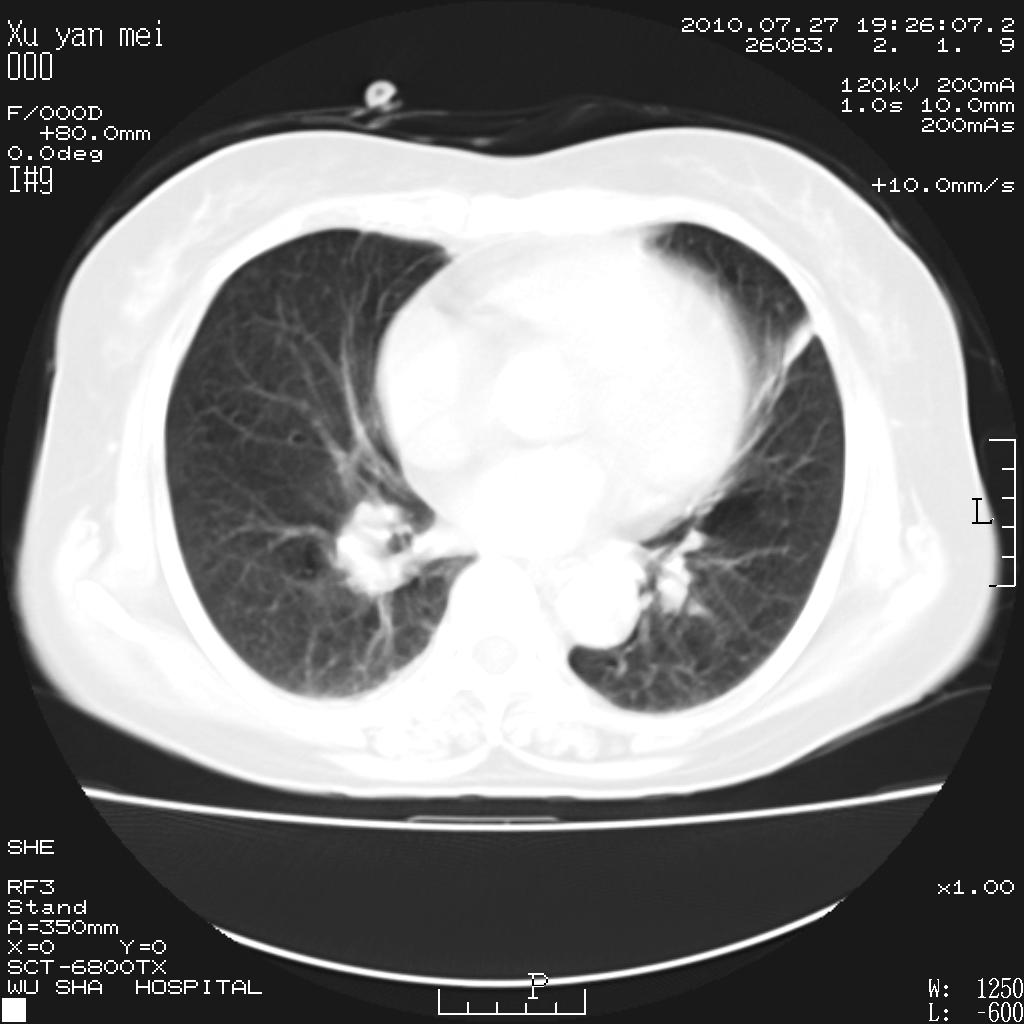

女,60岁,胸痛就诊,右肺结核?炎症?其它?(胸片右侧中上肺野确实看不到什么啊)

1)考虑两肺感染性病变;建议抗炎治疗后复查。2)双侧少量胸腔积液。

1)考虑两肺感染性病变;建议抗炎治疗后复查。2)右侧少量胸腔积液。

双肺炎症可能性大,建议抗炎后复查。右侧胸腔少量积液。双侧胸膜轻度增厚。

考虑两肺感染性病变;不除外肺栓;建议抗炎治疗后复查。